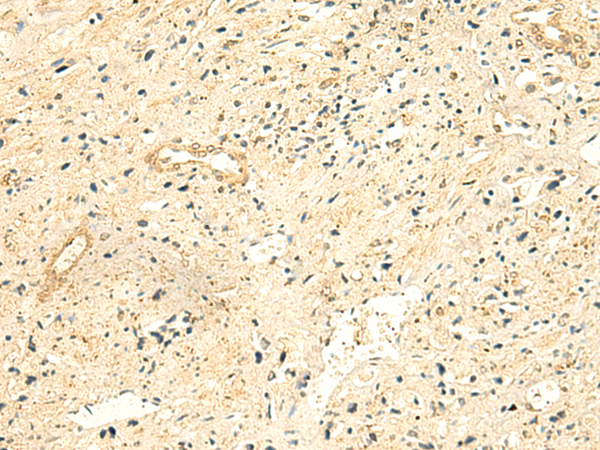

分类: 科研抗体货号: P10102别名: PFE; PTHR; PTHR1应用: IHC反应种属: Human, Mouse, Rat